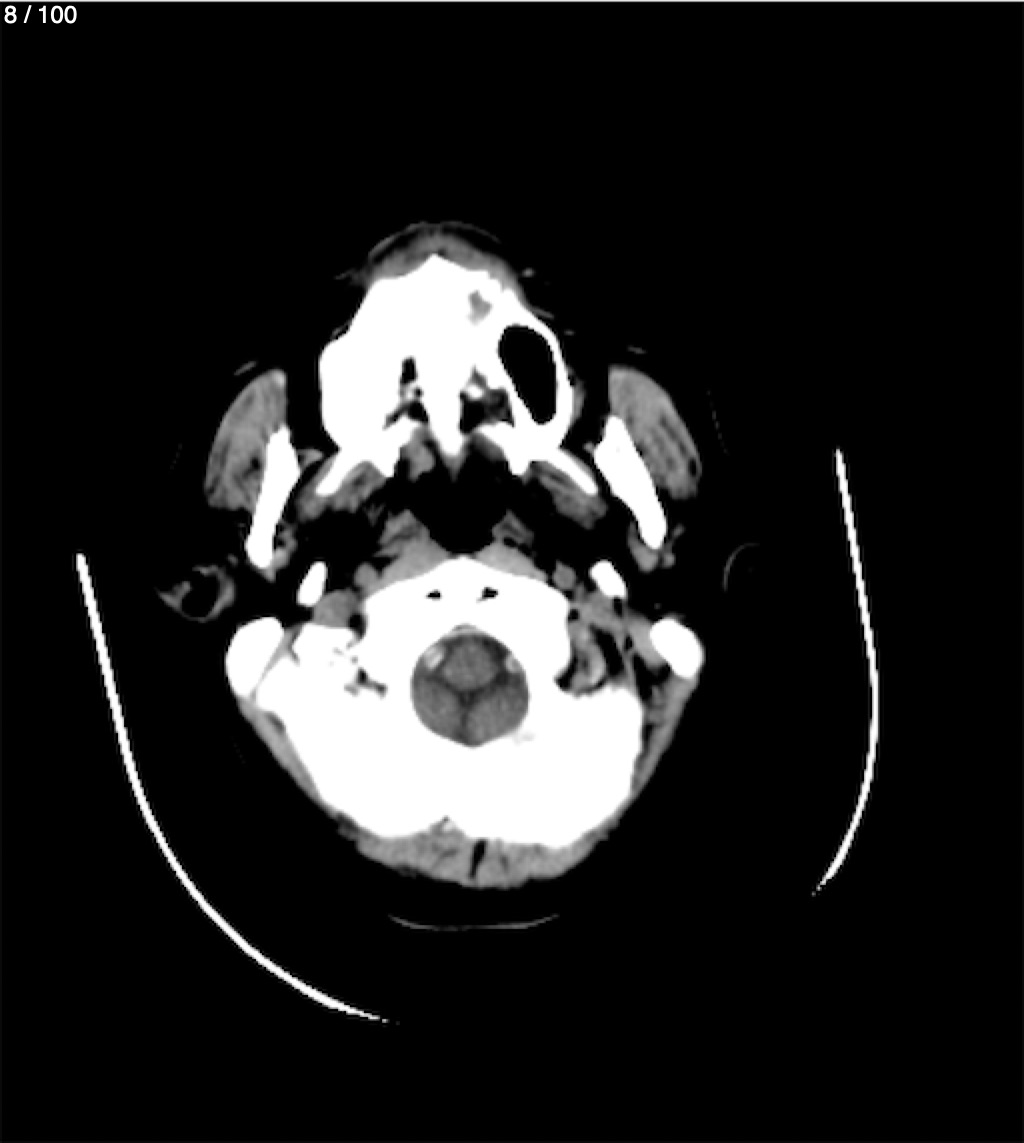

Valentin Perez Gomez 69A - T.C Craneo